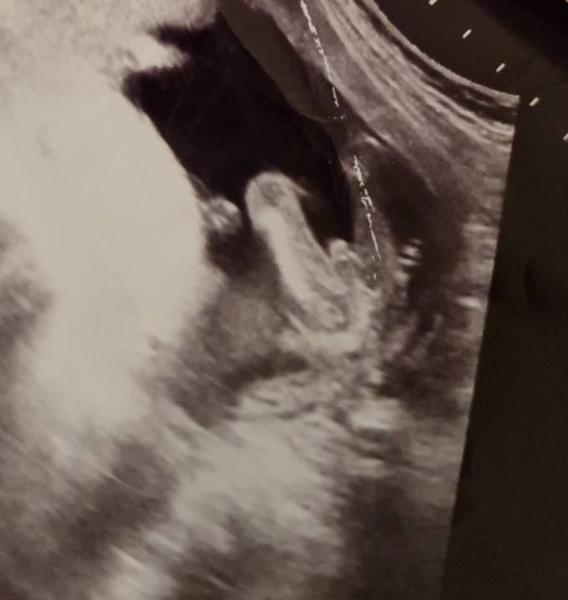

Also es sieht meinen sehr ähnlich war damals in der 23ssw bei der feindiagnostik 100% junge was die fruchtwasser Untersuchung danach auch nochmal bestätigte... also denke ein kleiner junge wird es bei dir

Bild zu

Eindeutig Junge Das ist unserer in der 20. oder 21. SSW